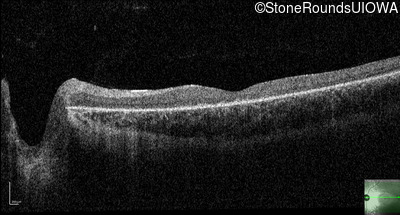

Optical Coherence Tomography - Left - 10/200

Exemplar / OCT Stack